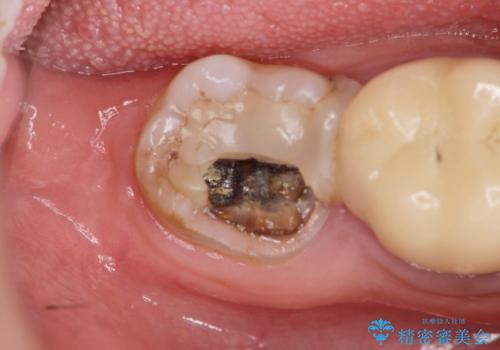

[ セラミック治療 ] 前歯の見た目を改善したい

- 前歯の色がばらばらで見た目が気になる、見た目の改善を希望され来院されました。

既に装着されていた金属を用いたセラミッククラウンの暗い色調とご自身の歯を白く、改善されたいと強く希望され

上下の前歯12本のセラミック治療を行なっていくこととなりました。

- 79.2万円(ジルコニアクラウン×6・仮歯×6)費用は治療当時の料金となります

![[ セラミック治療 ] 前歯の見た目を改善したいの治療前](https://seimitsushinbi.jp/wp/wp-content/uploads/2025/10/IMG_9990-2-500x350.jpg?v=1761816440)